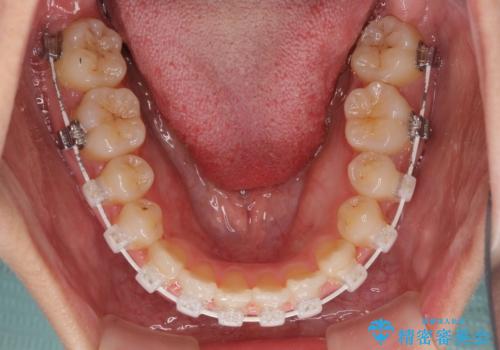

- 審美装置

マウスピース矯正の自己管理が面倒くさいことと、治療を早く終わらせたいとのことで、目立ちにくいワイヤー矯正にて歯列を整えることとしました。

1年半はかかると思っていた治療期間ですが、反対咬合となっている前歯が思いの外早く動き、僅か9ヶ月で終了させることができました。